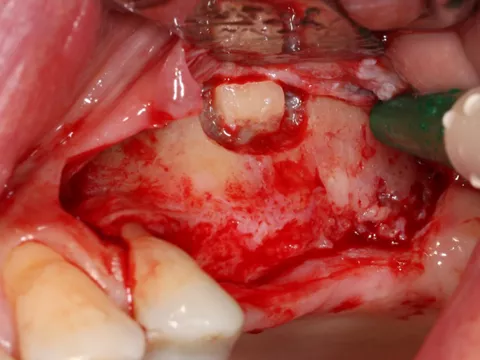

5. A full-thickness flap was elevated and a releasing incision made mesial to 24. Care must be taken at this stage not to damage the periosteum.

6. A lateral sinus lift was performed by creating a 7 × 5 mm window using a round tungsten carbide bur followed by a diamond bur.

7. The bony window was removed and placed in saline solution so that it could be placed back in position after grafting. The Schneiderian membrane was released without perforation.

8. The sinus was elevated with cortical/cancellous allograft of a particle size of 0.5 mm and volume of 1.5 cc.

9-10-11. The patient had D3 bone density. Hence an undersized drilling protocol was employed, the final drill diameter being one less than that of the implant. The green drill was used for the 25 implant (diameter 3.4) and the red one for the 26 (diameter 4.0).

12a-b-c. The design of the Axiom X3® ensures atraumatic implant placement with the micro motor. The Axiom X3® also preserves bone, even if the ridge is thin and resorbed. Despite the meager quantity of vestibular cortical bone, there was no perforation or rupture of the crestal margin.

13. The implants were placed 0.5–1 mm subcrestally. Note the thinness of the vestibular cortical bone at the 25 implant on this occlusal view. Despite this, we achieved perfectly acceptable stability values of 19 and 20 Ncm.

14. Graft material added to the vestibular aspect of 25 to offset the bone loss and ensure long-term implant survival.

15. The surgical site was closed with 5/0 non-absorbable monofilament polypropylene sutures, removed 10 days postoperatively. The implants were buried with their closure screws.